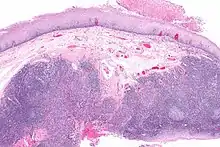

A large squamous cell carcinoma of the tongue as seen on CT imaging

Histopathologic appearance of a poorly differentiated squamous cell carcinoma specimen. Hematoxylin-eosin stain. p16 positive, EBV negative

Diagnosis of oral cancer is completed for (1) initial diagnosis, (2) staging, and (3) treatment planning. A complete history, and clinical examination is first completed, then a wedge of tissue is cut from the suspicious lesion for tissue diagnosis. This might be done with scalpel biopsy, punch biopsy, fine or core needle biopsy. In this procedure, the surgeon cuts all, or a piece of the tissue, to have it examined under a microscope by a pathologist.[34] Brush biopsies are not considered accurate for the diagnosis of oral cancer.[35] Salivary biomarkers are also being under investigation with emerging outcomes and could potentially be used as a non-invasive diagnostic tool in the future.[36]

With the first biopsy, the pathologist will provide a tissue diagnosis (e.g. squamous cell carcinoma), and classify the cell structure. They may add additional information that can be used in staging, and treatment planning, such as the mitotic rate, the depth of invasion, and the HPV status of the tissue.